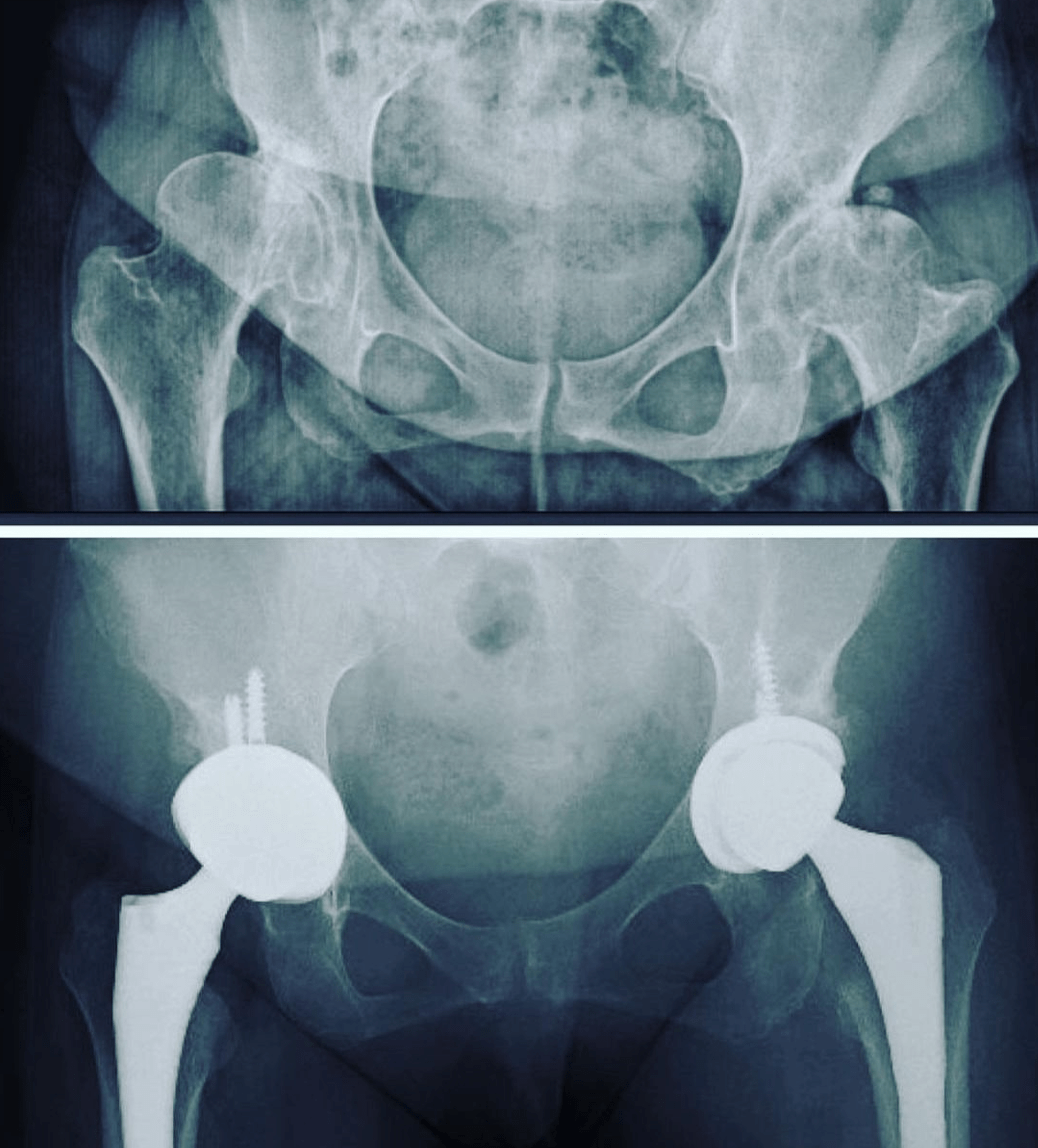

Замена обоих тазобедренных

Замена обоих тазобедренных 111 фотографий